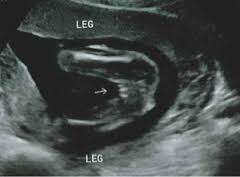

maluszek bezwiata szans na fikanie bo jest wcisniety do macicy lezy główka w dol obrocony do swiata i nozkami moze pofikac